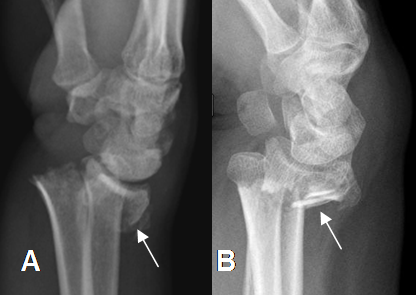

Fig 34. Fractura de Colles.

A: y B: Rx lateral. Fractura de Colles, con desplazamiento posterior del fragmento distal del radio.